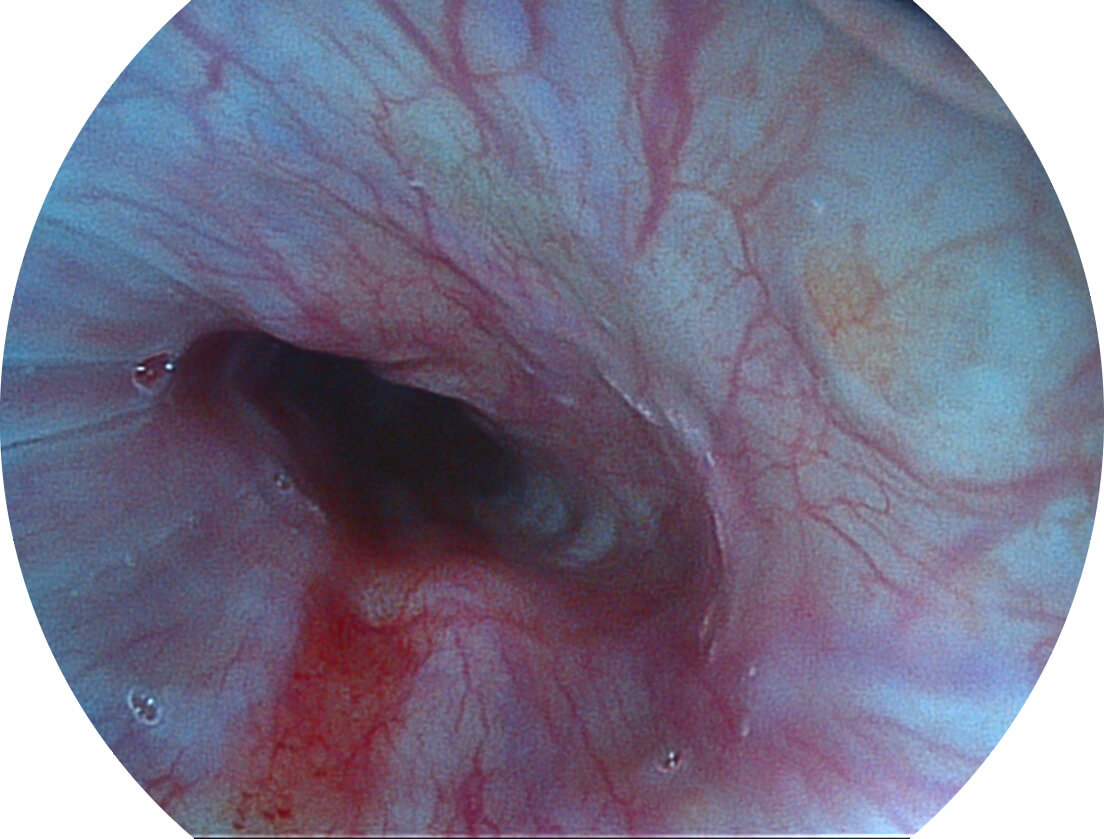

Spectral Focused lmaging, SFI

图像具有高亮度、高黏膜血管颜色对比度的特点,且不改变粘液、食物残渣、粪便的基本颜色,可在中远景下进行观察,助力消化道早期疾病的诊断。

白光图像

SFI图像

采用光路合束技术,光谱自由度高,实现了更丰富的照明模式,染色模式SFI及VIST,从远景到近景,助力消化道早期疾病诊断。